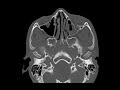

Orbital Floor Fracture

These images demonstrate downward buckling of the inferior orbital wall involving the medial aspect of the infraorbital canal compatible with fracture. There is associated downward herniation of fat as well as the inferior rectus muscle into the left maxillary sinus. Herniation of the inferior rectus may lead to entrapment which is a purely clinical diagnosis. This patient had evidence of entrapment on clinical exam and presented with restricted upward gaze. These type of fractures usually result from a direct blow to the orbit. Approximately 50% will be associated with medial orbital wall fracture. The infraorbital canal is a site of weakness.